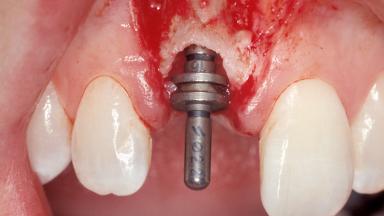

Immediate Placement of an Implant in a Maxillary Right Central Incisor Site

A 30-year-old female patient was referred to the office for the treatment of tooth 11. Her chief concern at the initial visit was to inquire, “Why is my tooth pink?” Upon clinical examination, it was determined that tooth 11 had a previous history of trauma and that the clinical crown had become noticeably pink in color as a result of internal resorption. This diagnosis was confirmed radiographically, indicating a large radiolucency involving the central and distal portions of the clinical crown. It was determined that restoration of this tooth was not possible, and that extraction was indicated. The presence of a mid-line diastema, which the patient wanted to reproduce, directed the treatment plan for tooth replacement utilizing a dental implant.